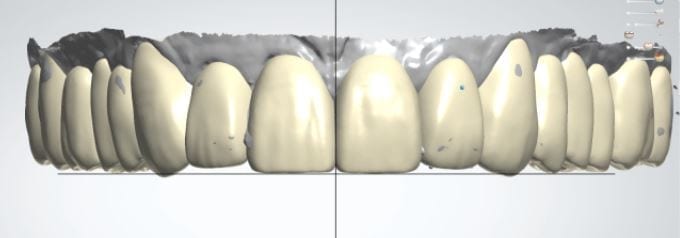

The digital models were then imported into a third party software where a library of tooth morphologies are available for the clinician to choose from.

Once the appropriate library is chosen, the digital wax ups are performed. In the subsequent photos you can see the transparent overlay of the wax-ups to the original position of the existing dentition